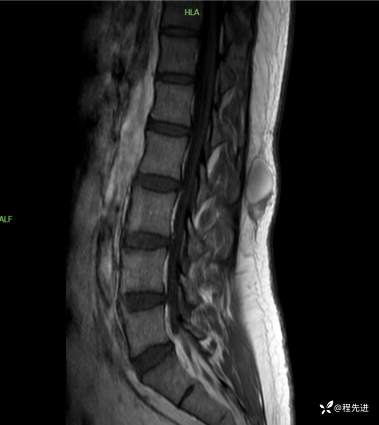

T2矢状位:

T2压脂矢状位:

T1矢状位:

T1增强矢状位:

T1增强压脂矢状位: